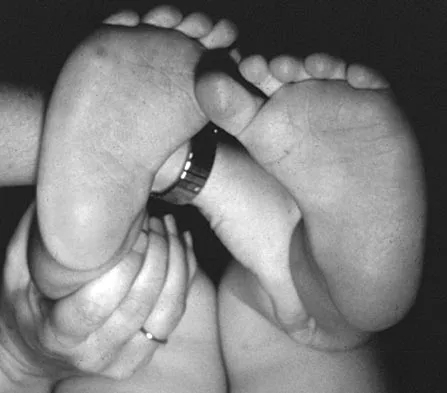

An 11-year-old girl sustained an injury to her right foot when a 500-lb headstone fell on it. The headstone was removed after 3 minutes. Radiographs show multiple midfoot fractures. Examination reveals severe pain that is worse with passive toe motion. Clinical photographs are shown in Figure 28. Management should consist of

Explanation